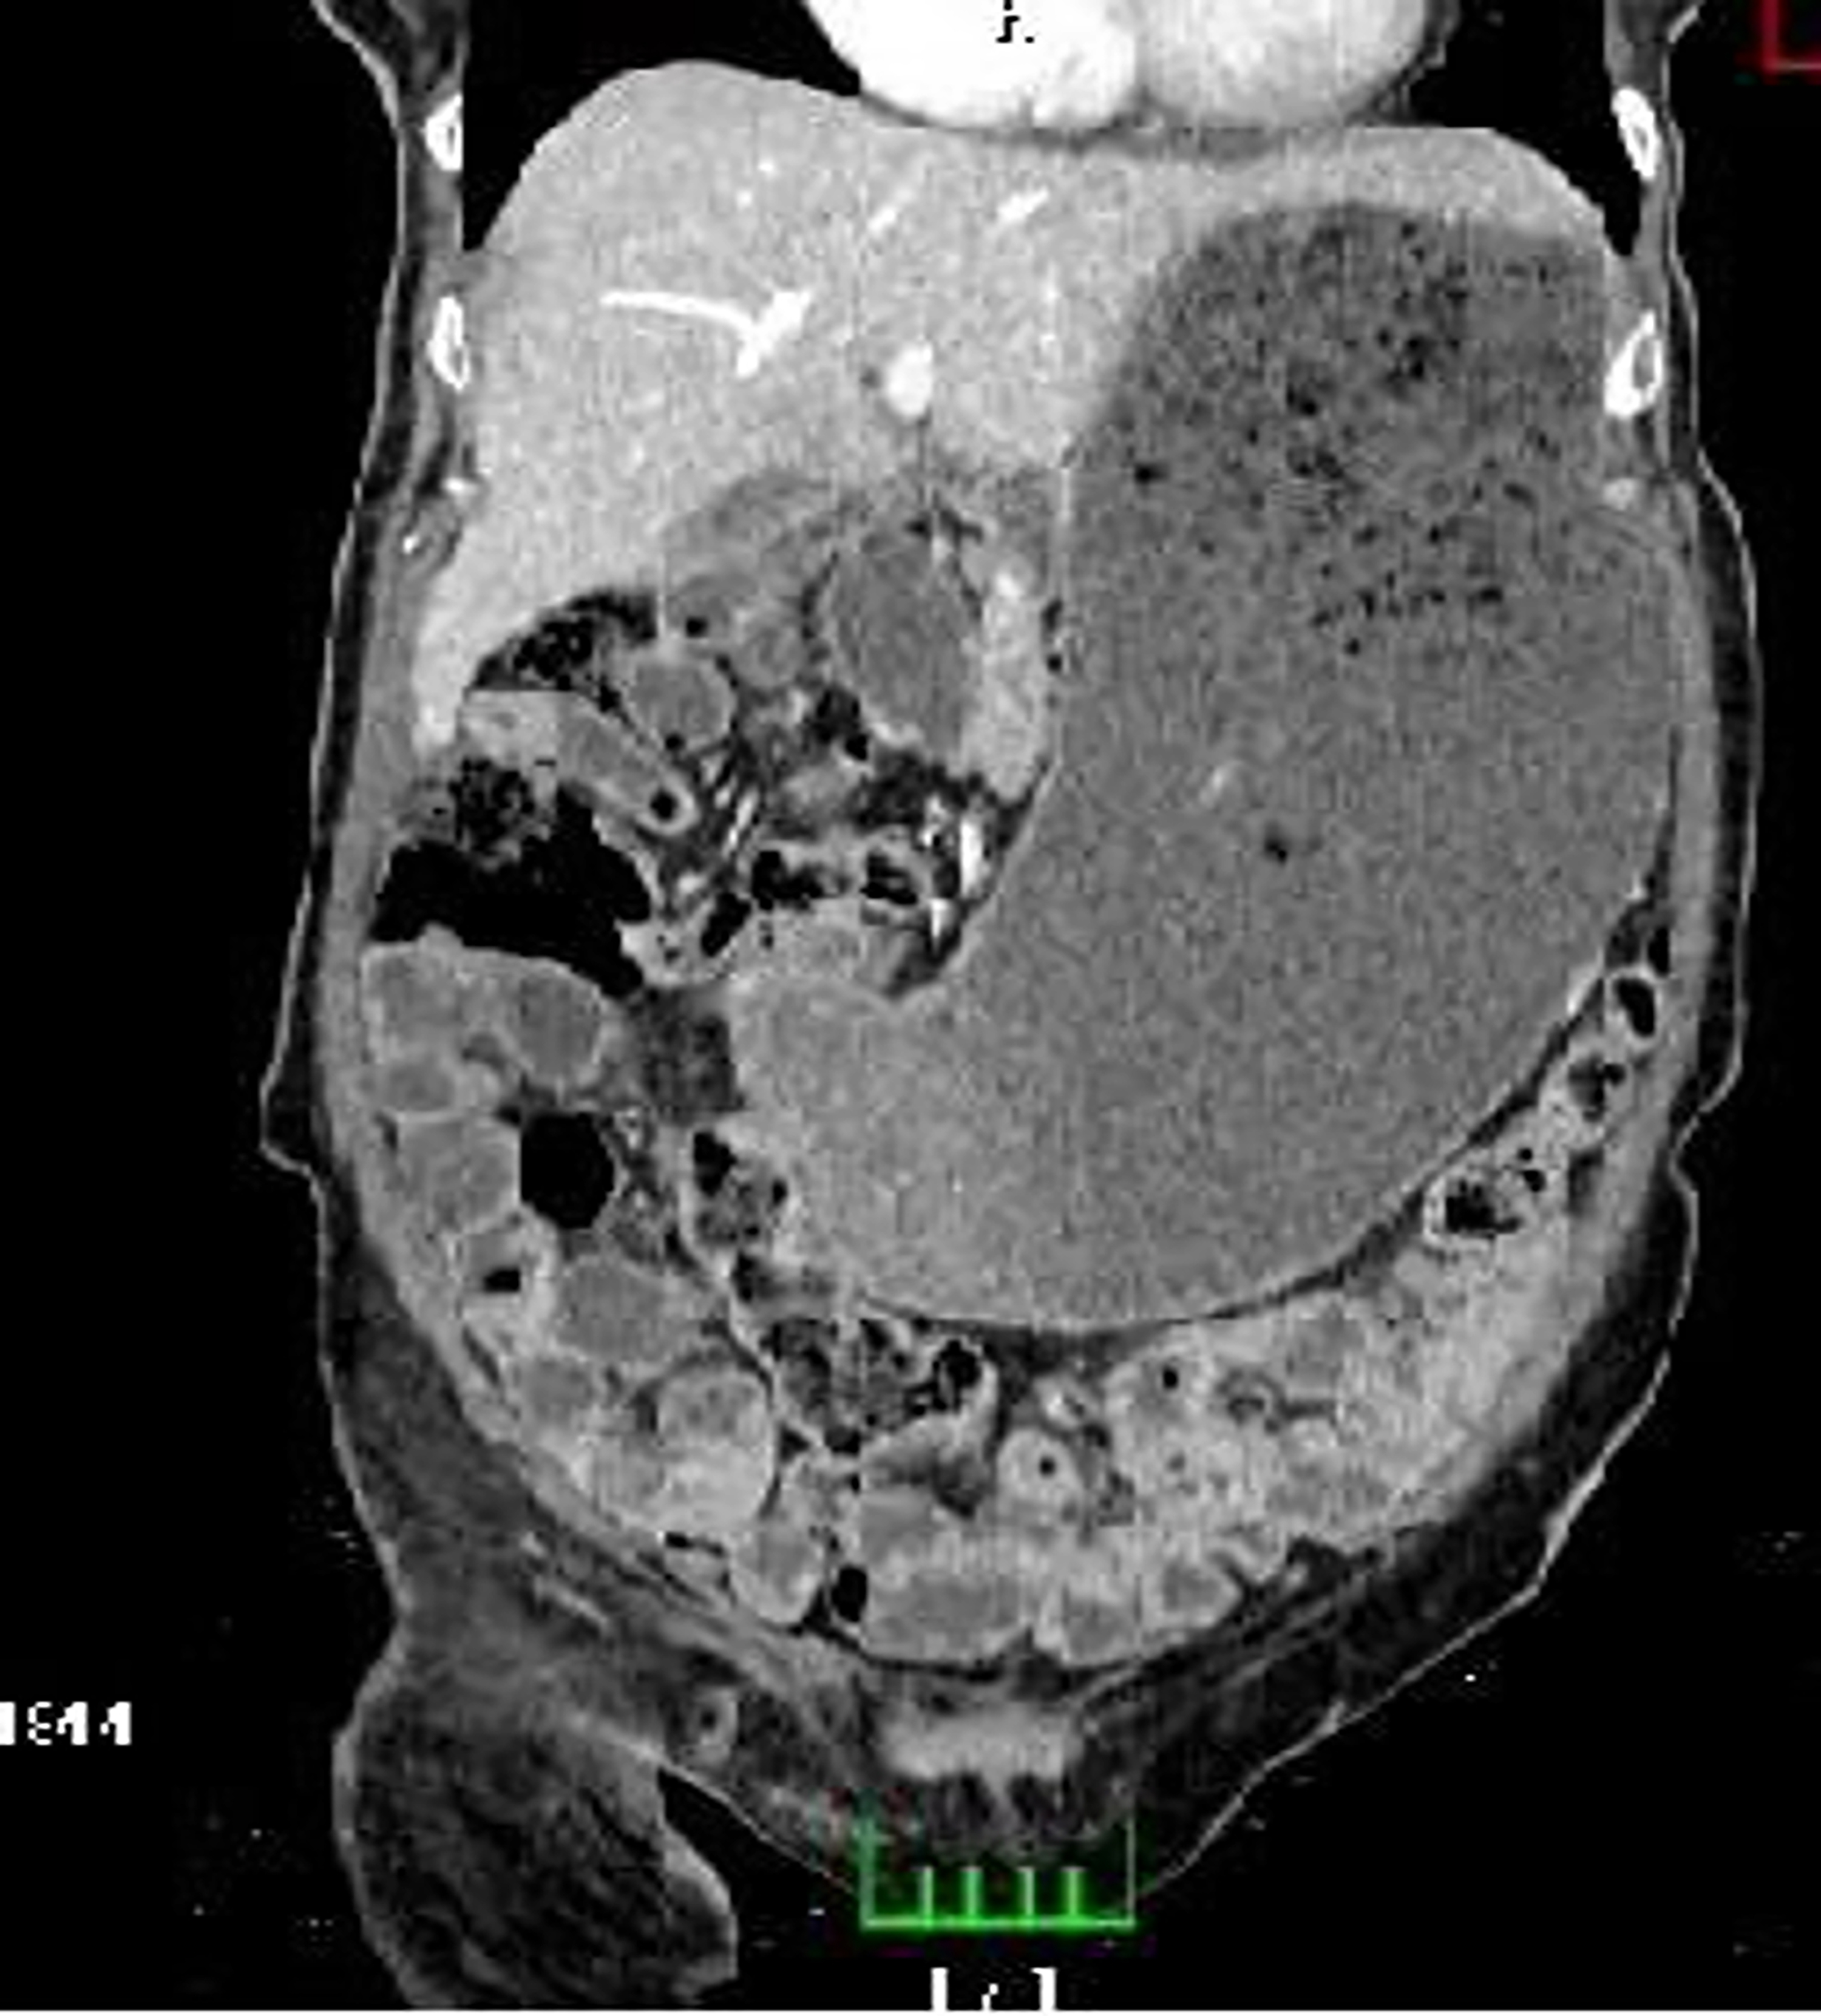

Abdominal CT angiography revealed no thrombus or ischemic findings in the vessels or intestines, but the stomach was distended with dense content (Figure 1, Figure 2). The stomach appeared to be in a hypotonic state, and its size extended to the pelvis. Diabetic gastroparesis was suspected, and the patient was admitted to the general surgery ward for treatment and follow-up.

In one case, a barium study showed a decreased gastric emptying rate and gastric dilation.4 In another, a barium radiologic examination revealed the absence of esophageal peristalsis, gastric dilation, and solid food remnants.5 In a case reported by Tonzi et al., after no improvement with frequent and small meals, an endoscopy was performed, revealing an incompetent lower esophageal sphincter and undigested food particles in the stomach, leading to the diagnosis of diabetic gastroparesis. In our case, abdominal CT angiography showed a distended abdomen with dense content, and no further tests were performed since gastroparesis was suspected based on the CT findings. Dynamic contrast imaging was used to observe the progression of contrast through the gastrointestinal system.

Figure 1. Transverse plane of the stomach on abdominal CT

Figure 2. Coronal plane of the stomach on abdominal CT